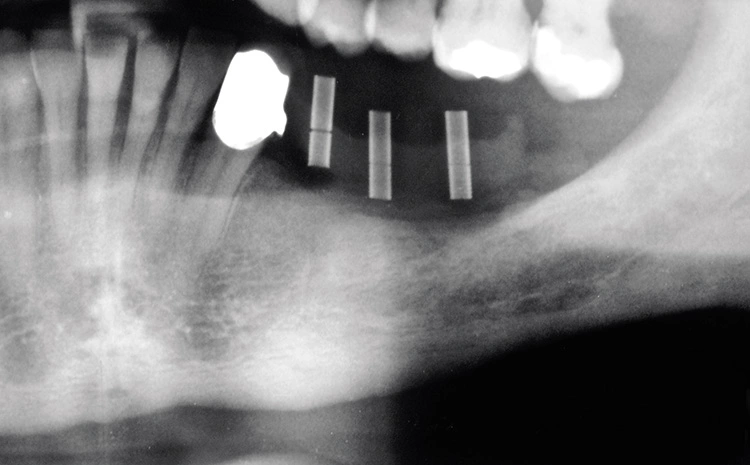

Bei der Vorstellung des Patienten zeigte sich ein qualitatives und quantitatives Knochen- und Weichgewebedefizit im linken Unterkiefer (34–37). Der Zahnverlust lag mehrere Jahre zurück und der Patient wünschte eine festsitzende Versorgung. In der radiologischen Diagnostik zeigte sich ein hochliegendes Foramen mentale.

Präoperativ wurde im Sinne eines Backward Planning erst die spätere Implantatposition und in Kenntnis dieser, die Ausdehnung des Titangitters festgelegt. Hierbei wurde festgestellt, dass sich zum einen das Foramen mentale direkt im Augmentations- und Implantationsbereich befindet und zum anderen der Verlauf des Nervus alveolaris inferior, trotz Augmentation, nur relativ kurze Implantate zulassen wird.